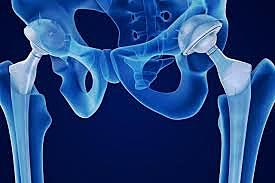

Giliberti y Bateman, desarrollaron los prototipos de las actuales endoprótesis bipolares, empleando copas metálicas revestidas con polietileno de alta densidad y cerradas sobre la cabeza del componente femoral,Este dispositivo se ha utilizado en una gran variedad de intervenciones primarias y secundarias de cadera